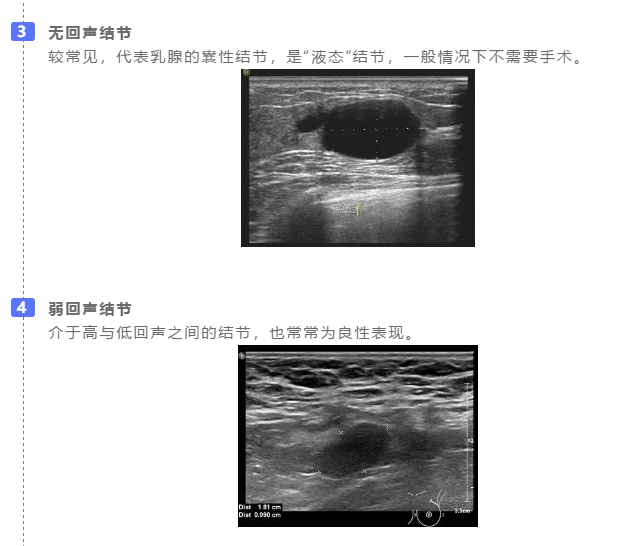

3回声

在乳腺超声报告中,结节一般有四种回声: